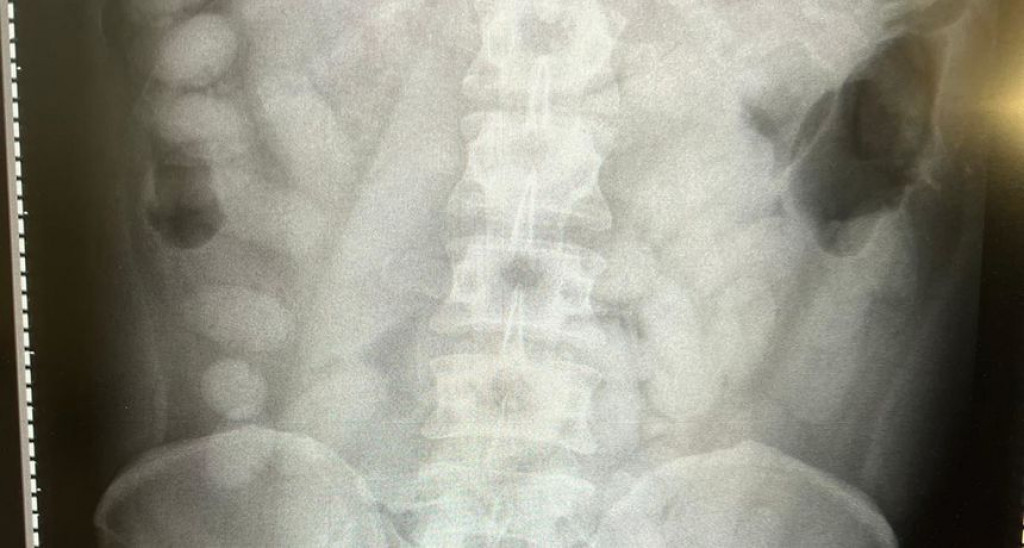

Mostarac je tom prilkom progutao dva paketića sa sadržajem nepoznate bijele materije. Mladić je nakon toga upućen u Sveučilišnu kliničku bolnicu Mostar gdje su mu od strane liječnika odstranjena dva strana tijela iz želudca nakon čega je zadržan u bolnici.